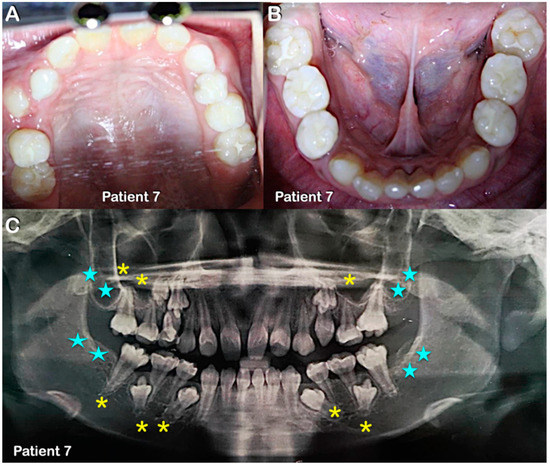

Figure 6.

Patient 7 in mixed dentition. (A,B) Round-shaped permanent molars and molars with multiple supernumerary cusps. (C) Panoramic radiograph showing agenesis of second and third permanent molars (blue stars) and single-rooted primary and permanent molars (yellow asterisks).